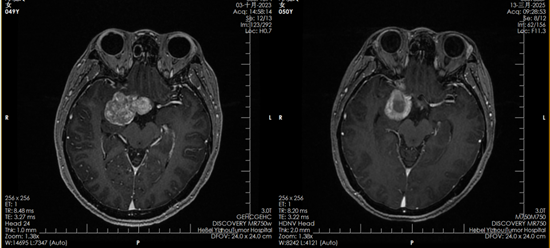

2023年10月,鄧女士正式開始質(zhì)子治療。一個多月里,她接受了30次治療?!爸委煹臅r候一點感覺都沒有,就像躺下來休息一會兒。要不是看到復(fù)查影像里的腫瘤變化,我都不敢相信這是真的?!编嚺空f。

質(zhì)子治療前后對比影像

如今,復(fù)查影像顯示腫瘤已被有效控制,她的堅持終于換來了可喜的結(jié)果。